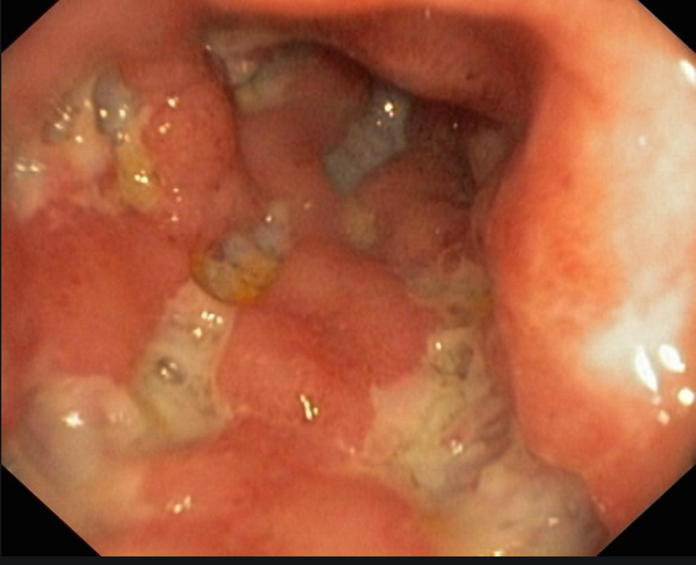

Der Morbus Crohn ist eine chronisch entzündliche Darmerkrankung mit bevorzugtem Erkrankungsalter im 2.-3. Lebensjahrzehnt, selten sind auch spätere Manifestationen möglich. Die Erkrankung kann im gesamten Verdauungstrakt, also vom Mund bis zum Enddarm auftreten. Bevorzugte Region für einen Crohn-Befall sind der Übergang von Dünn- zu Dickdarm (terminales Ileum) und der Dickdarm vor allem im Bereich des Darmausgangs (Anus).

Typisch ist ein diskontinuierlicher Befall, das heißt neben erkrankten Abschnitten finden sich auch gesunde Anteile. Im Gegensatz zu Colitis ulcerosa, die auf die Schleimhaut begrenzt ist, sind beim Morbus Crohn immer alle Wandanteile des jeweiligen Darmabschnittes betroffen.

Die wichtigsten Untersuchungsverfahren stellen die Endoskopie (Magenspiegelung, Dickdarmspiegelung) sowie das MRT mit Darstellung des Dünndarmes als sogenanntes Hydro-MRT. Selten ist eine Dünndarmspiegelung als Kapselendoskoopie oder sog. Doppelballonendoskopie erforderlich.